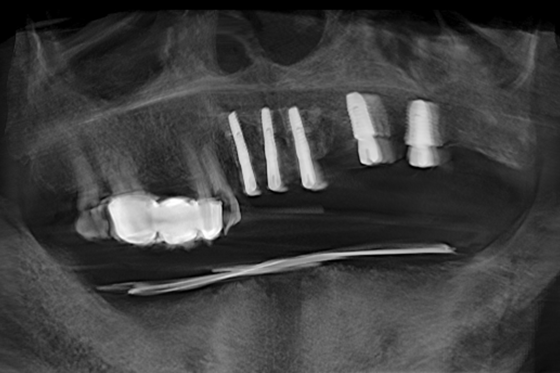

种植体植入术后照片

短短的不到一小时,向峰团队顺利为蔡老先生完成了5颗种植牙手术。术中采用动态心电监护系统,通过闭环式氧疗管理,实现手术期间生命体征的精准调控与双重保障。